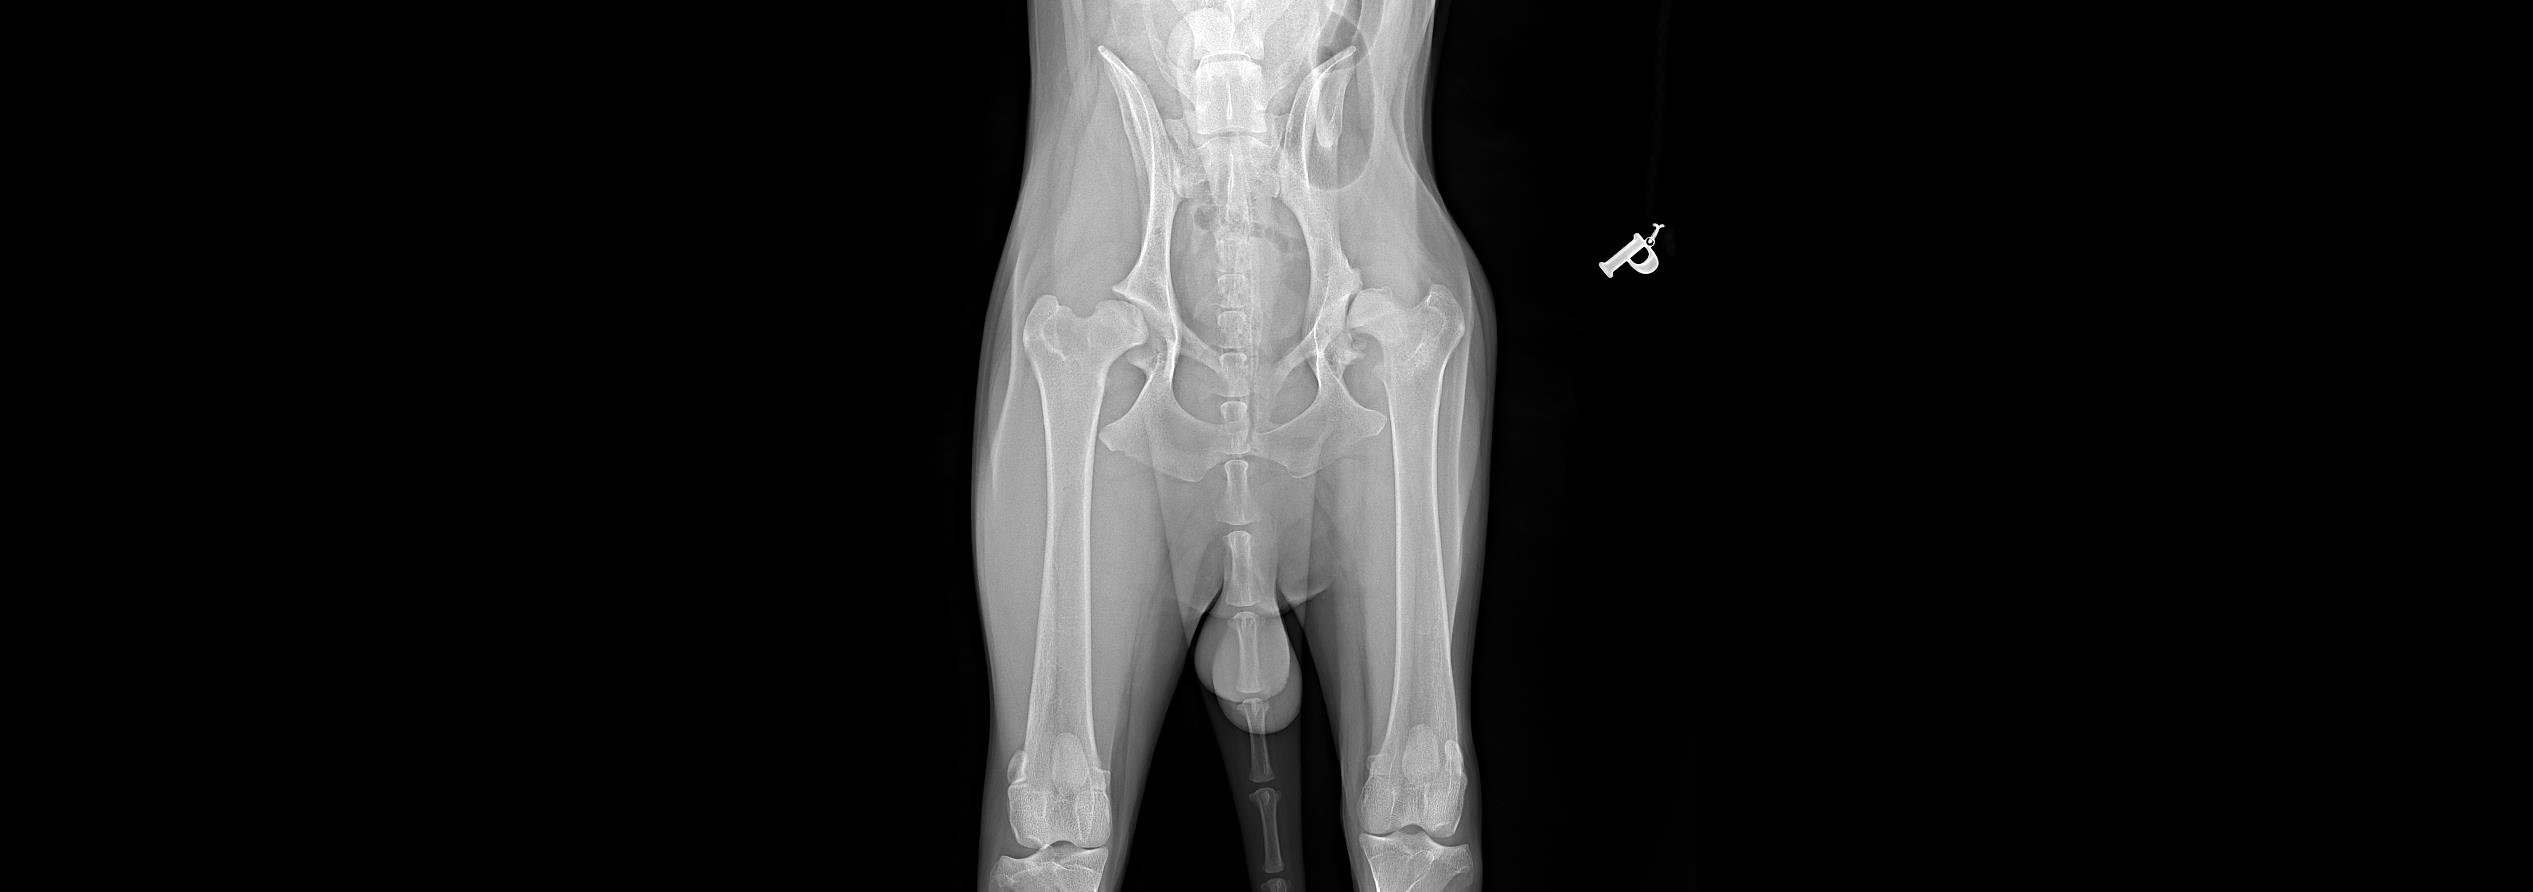

Jesteśmy totalnie załamani bo finanse naszej rodziny są w fatalnym stanie...a ze względu na to że Jamal cierpi,coraz gorzej chodzi operacja przydałaby sie jak najszybciej..Dzięki Waszym wielkim sercom udało się uzbierac na zrobienie prześwietlenia...Wierzę w Was ze i tym razem pomożecie udostępniając link zbiórki a i kazda złotówka się liczy!!Prosze pomózcie naszemu Jamalowi aby mógł znowu biegać i być szczęśliwym psem..Szczęśliwy pies to szczęśliwy własciciel. Zapraszam do obejrzenia krótkiego filmu w którym Jamal Wam wszystko opowie. Link do fimu znajdziecie na tej zbiórce. Dziękujemy!!!